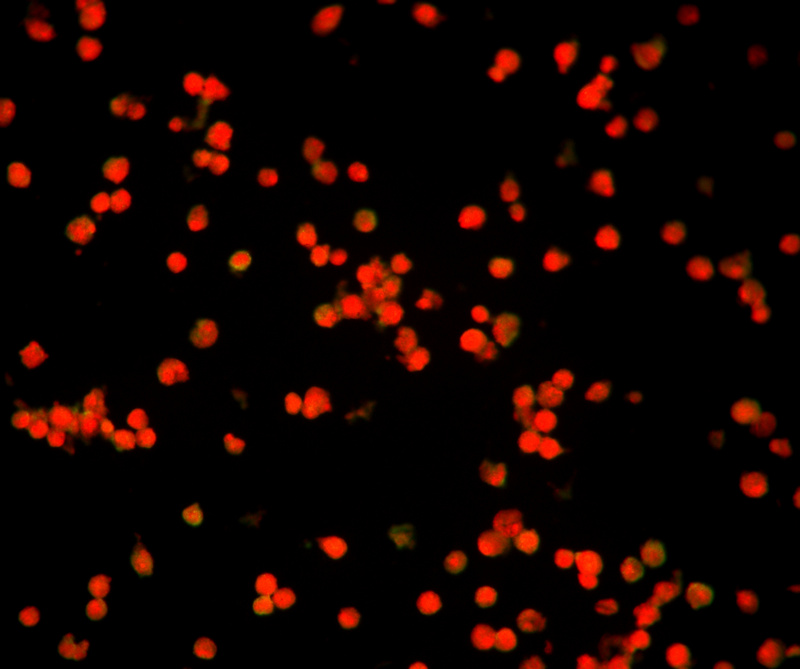

流感疫苗_06.jpg

流感病毒检测阴性

使用荧光显微镜400倍视野观察(40X物镜),甲型流感检测孔位荧光少且弱,视为阴性结果,荧光亮度强数量多,平均每个视野的阳性细胞大于3-5个,就可以判断为阳性。乙型流感另有一个孔位,判断标准和甲型流感一致。

流感疫苗_07.jpg

流感病毒检测阳性